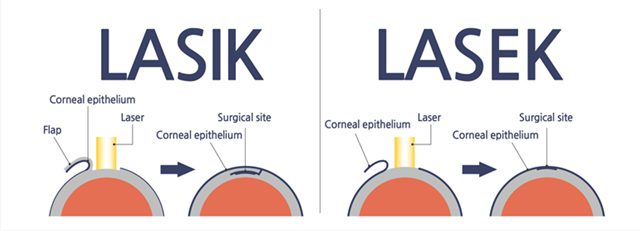

الفرق بين الليزر والليزك متعددة مثل:

الفرق بين الليزر والليزك للعين من ناحية الآلية

: فعملية الليزر تستخدم ضوء الليزر لعلاج تغير شكل القرنية والذي يؤدي لمشاكل في الرؤية مثل اللابؤرية وقصر النظر. بينما في الليزيك يتم استخدام أداة ذات شفرة رفيعة لعمل طرف في القرنية قبل أن يقوم ضوء الليزر الفوق البنفسجي بإعادة تشكيل القرنية.